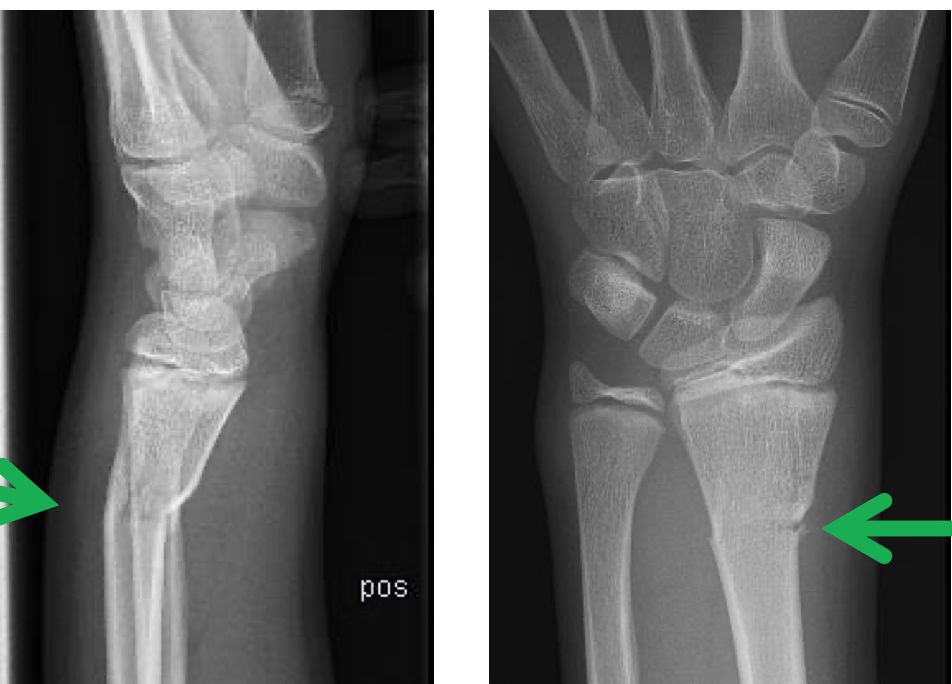

Hvordan klassifiseres håndleddsfrakturer?

Hvilke egennavn-frakturer har man?

Hva er indikasjon for å operere distal radius?

typisk ved

Hvordan burde frakturen være etter reponering?